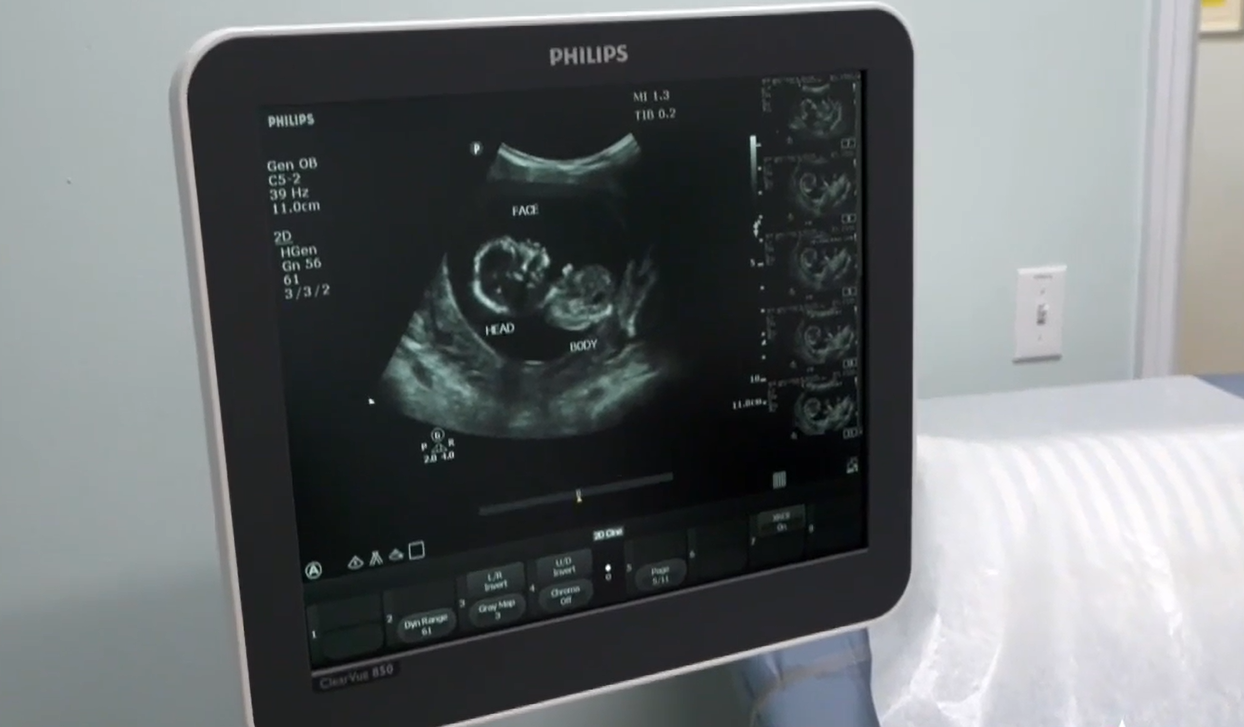

Hadro explained how sidewalk counselors regularly inform abortion-minded women headed for Planned Parenthood about the pregnancy help center nearby, and she said the clinic is equipped with an ultrasound and an ultrasound van to travel to women in need.

“And then get in contact with a nurse, get in contact with a doctor, get the progesterone that they need to take, come in for an ultrasound, and make sure that, everything will progress in a more positive way,” she said.

After starting the abortion pill reversal protocol, Metheny came to the Community Pregnancy Clinic for her follow-up ultrasound and received unexpected, wonderful news.

“When I came into this clinic,” Metheny said, “they told me instantly, they were like, ‘You're having twins,’ which was a complete to me, complete shock.”

“So not only had I saved one life,” she said, “not only was one life important to me, but I found out that there were two … two … yeah.”